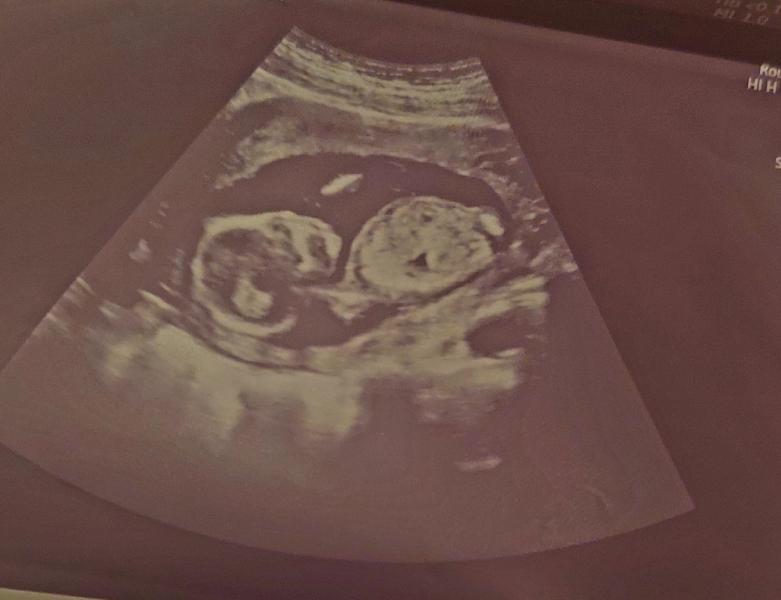

Первое фото УЗИ на 14 неделе беременности: что увидели, пол ребенка, ощущения?

Наше первое фото (14 неделя) 😊🥰